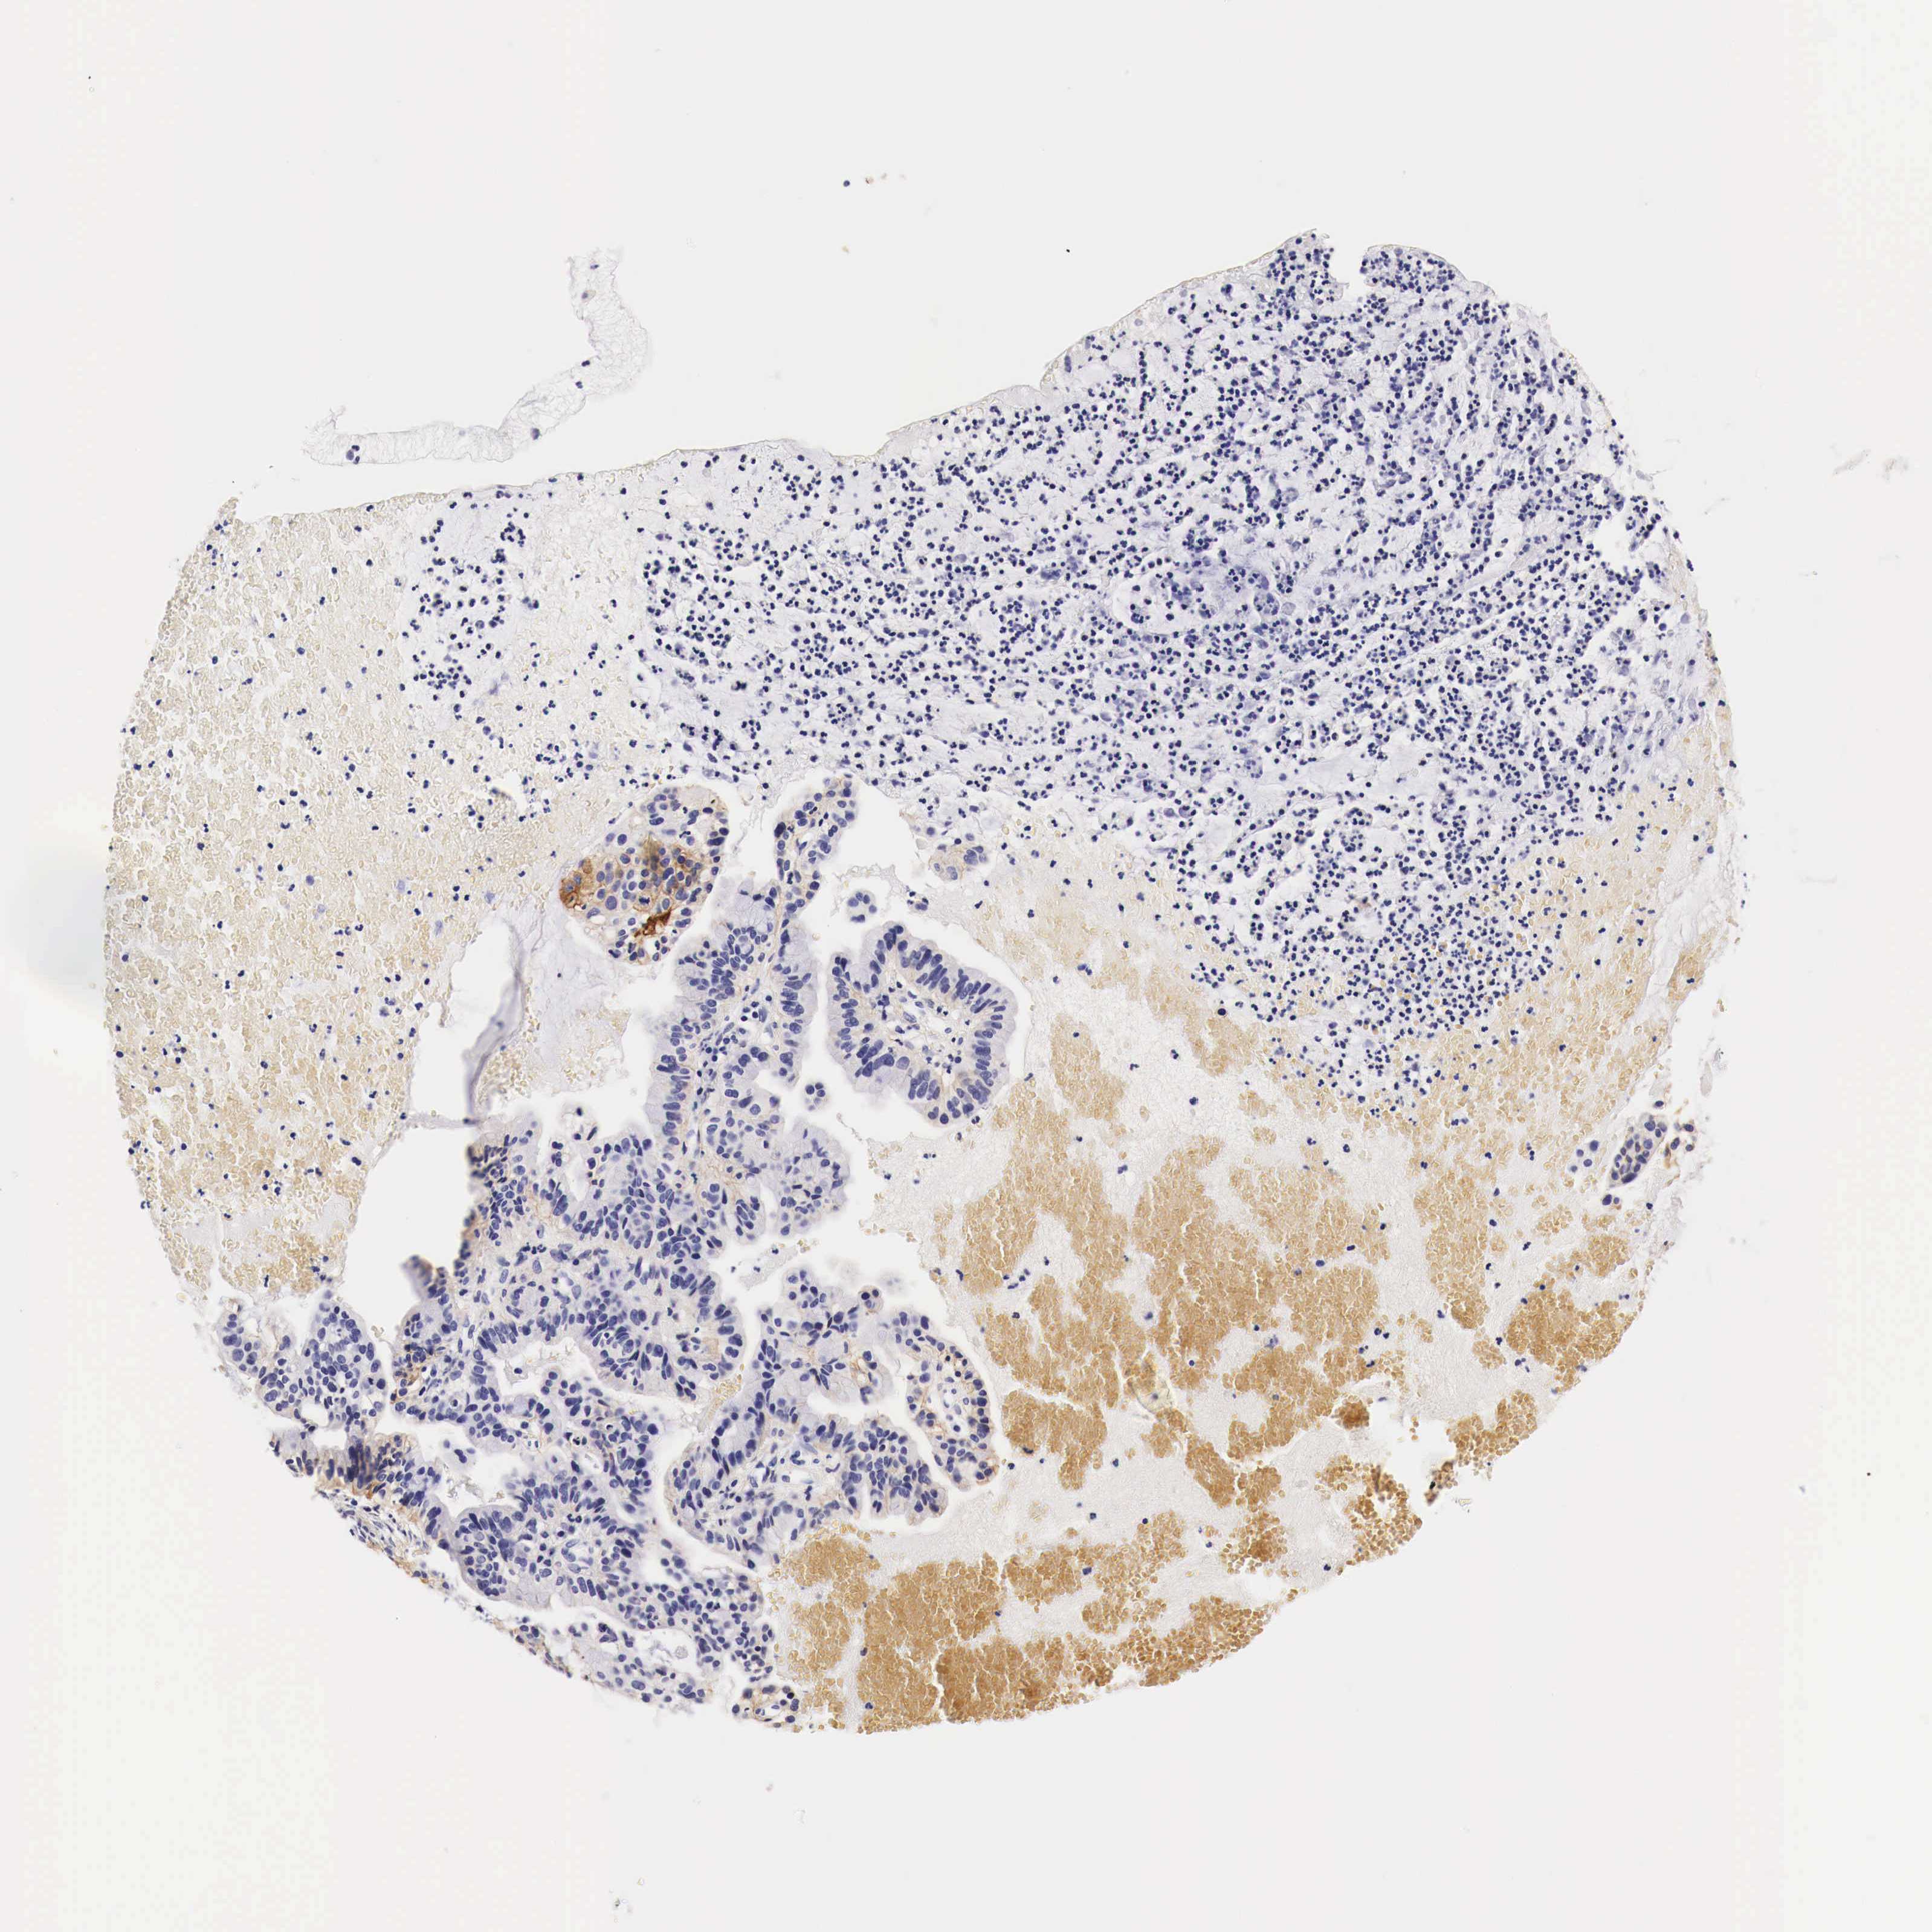

CERVICAL CANCER - Protein expressioni

A mouse-over function shows sample information and annotation data. Click on an image to view it in a full screen mode. Samples can be filtered based on level of antibody staining by selecting one or several of the following categories: high, medium, low and not detected. The assay and annotation is described here.

Note that samples used for immunohistochemistry by the Human Protein Atlas do not correspond to samples in the TCGA dataset.

Antibody stainingi

Antibody staining in the annotated cell types in the current human tissue is reported as not detected, low, medium, or high, based on conventional immunohistochemistry profiling in selected tissues. This score is based on the combination of the staining intensity and fraction of stained cells.

Each image is clickable and will lead to virtual microscopy that enables deeper exploration of all samples and also displays staining intensity scores, fraction scores and subcellular localization as well as patient and tissue information for each sample.

HPA001200

HPA018530

CAB000035

CAB068186

CAB073534

CAB080313

CAB080314

CAB080473

CAB080475

CAB080506

CAB080507

CAB080509

CAB080510

CAB080511

Staining

High

Medium

Low

Not detected

Intensity

Strong

Moderate

Weak

Negative

Quantity

>75%

75%-25%

<25%

None

Location

Nuclear

Cytoplasmic/membranous

Cytoplasmic/membranous,nuclear

Adenocarcinoma, NOS

Squamous cell carcinoma, NOS